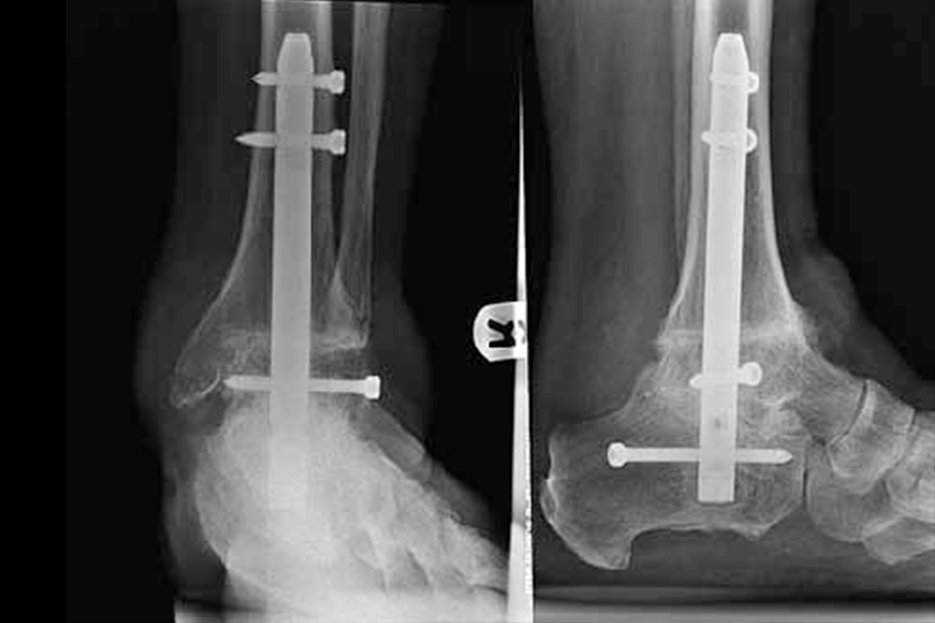

OSTEOTOMIE I ARTRODEZY OKOŁOKOSTKOWE

Są to kompleksowe zabiegi stosowane w leczeniu pacjentów z zaawansowanymi zmianami zwyrodnieniowymi, dysplastycznymi lub/i pourazowymi stopy i stawu skokowego. Procedury te obejmują osteotomię korekcyjną pięty, osteotomię nadkostkową, artrodezę (fuzję) st. skokowego i stopy uwalniając pacjenta od dolegliwości bólowych związanych z deformacją stawów. Podczas zabiegu wykorzystuje się implanty tytanowe takie jak śruby, gwoździe i płytki.